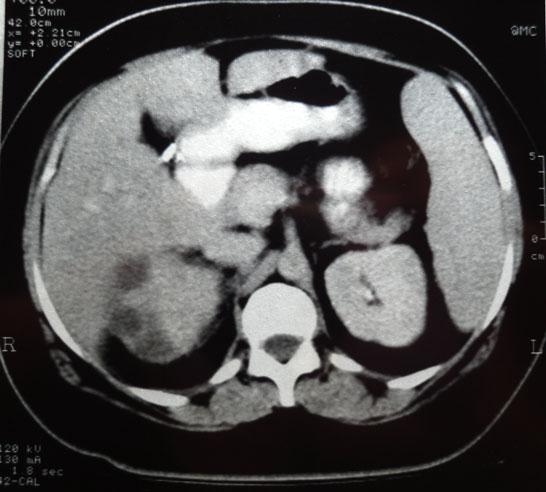

Chronological Photo-sequence

of the case progression

-On presentation: